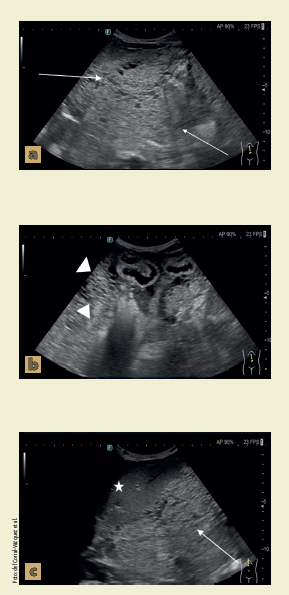

Un paciente mexicano de 53 años de edad, con antecedente de alcoholismo crónico, acudió por presentar desde hacía 2 meses aumento del perímetro abdominal, pérdida ponderal y anorexia, con el antecedente previamente descrito y la asociación sindromática se sospechaba de una probable cirrosis alcohólica asociada a hipertensión portal y ascitis en la cavidad abdominal, motivo por el cual se solicita un ultrasonido de hígado y vías biliares (figura 1) para orientar el tratamiento; con resultado de lesión de componente mixto (sólido y quístico) dependiente del peritoneo el cual provoca invasión a órganos sólidos (hígado y bazo).

Figura 1 La imagen a corresponde a un ultrasonido donde se visualiza lesión dependiente de mesenterio (→) de ecotextura heterogénea con zonas sólidas y quísticas, en la imagen b y c se visualizan asas de intestino delgado (➤) y el lóbulo hepático izquierdo con pérdida de la interfase entre la lesión y los órganos.